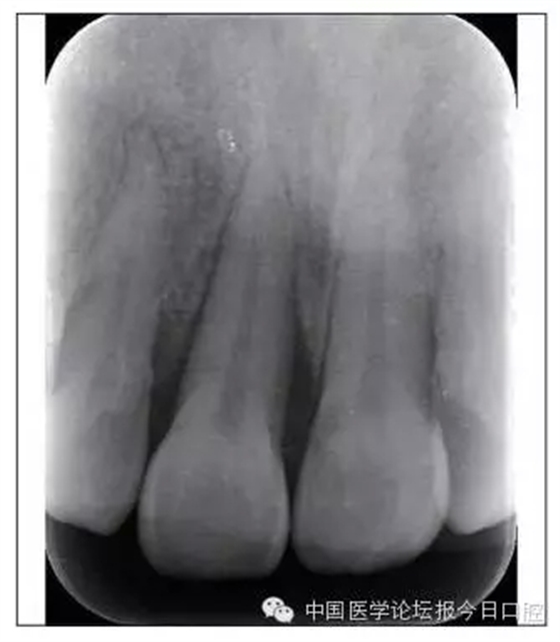

本病例為慢性牙周炎致前牙漂移、深覆(牙合)患者。本病例采用無托槽隱形矯治技術(shù)進行治療。無托槽隱形矯治器具有可摘戴、便于口腔衛(wèi)生維護和牙周治療的優(yōu)點,更適合于伴有牙周炎的錯(牙合)畸形患者的治療。 患者男,48歲,前牙有縫、前突求診。 患者面部對稱,側(cè)面觀上頜前突,下頜后縮。 口內(nèi)情況:恒牙列,24、34、44缺失,磨牙Ⅲ類關(guān)系,上牙列散隙,上前牙扇形漂移。前牙深覆(牙合)、深覆蓋??谇恍l(wèi)生較差,11與12間牙齦乳頭紅腫,多個牙探診有牙周袋形成,11松動Ⅰ度,余切牙松動(-),患者面像及口內(nèi)像如圖1、2所示。 圖1 治療前面像 圖2 治療前口內(nèi)像 全口曲面體層片(圖3)顯示,患者全牙列牙槽骨吸收;根尖片(圖4)示11近中牙槽骨角形吸收已達根尖1/3,21牙槽骨嵴頂吸收至根1/2,23牙槽骨近中骨板角形吸收至根1/2。磨牙區(qū)骨嵴頂吸收3mm。治療前頭顱側(cè)位片見圖3,治療前ODS模型見圖5。 圖4 治療前根尖片 圖5 治療前ODS模型 牙型:安氏Ⅲ類。骨型:Ⅱ類。面型:上頜前突,下頜后縮。 問題列表為:①上牙列間隙;②上切牙病理性牙移位;③前牙深覆(牙合)、深覆蓋;④24、34、44缺失;⑤慢性牙周炎。 矯治目標包括:①排齊牙列,關(guān)閉牙列間隙;②改善前牙深覆(牙合)、深覆蓋;③改善牙周狀況。 矯治設(shè)計有:①牙周基礎(chǔ)治療與維護。②壓低、內(nèi)收上切牙,關(guān)閉上牙列間隙。③壓低下切牙,伸長下后牙,整平Spee曲線,改善前牙覆(牙合)、覆蓋。 患者進行全口齦上潔治、齦下刮治,口腔衛(wèi)生宣教,并按牙周醫(yī)師的要求,每2~3個月行牙周檢查與治療。 牙周基礎(chǔ)治療結(jié)束3個月,開始隱形矯治。于14、25、35、36、45、46上粘接附件(圖6),于16、26(牙合)面粘接(牙合)墊。 圖6 ODS設(shè)計附件粘接圖示 矯治過程中注意(牙合)墊是否脫落或磨損,及時修補。 注意上前牙內(nèi)收時有無咬合干擾,及時調(diào)(牙合)。下頜前磨牙伸長到位后,磨除16、26(牙合)墊。 下頜佩戴第24步矯治器時,分別在36、37、46、47的頰、舌側(cè)粘接舌扣,矯治器上預(yù)留伸長空間,用3/16英寸、3.5盎司皮圈牽引,輔助伸長下磨牙(圖7)。 患者共戴用矯治器上頜32步,下頜26步。 矯治后,牙列間隙關(guān)閉,面型及覆(牙合)覆蓋改善。11根尖片(圖8)顯示,治療后較治療前,牙周支持組織增加,牙槽骨角形吸收區(qū)水平向縮小0.3mm,垂直向縮小0.6mm。11松動Ⅰ度,余切牙無松動。 圖8 治療后根尖片 圖9 治療后口內(nèi)像 圖10 治療后X線檢查 圖11 治療后ODS模型 正畸-牙周聯(lián)合治療對于牙周組織的影響 多學(xué)科綜合治療牙周炎患者不再是正畸治療的禁忌證。良好的牙周治療為正畸治療中的牙齒移動打下堅實基礎(chǔ),而正畸治療排齊牙齒、去除(牙合)干擾,有利于牙周健康。 牙周炎患者的正畸治療必須在牙周炎癥得到控制后才能進行,否則,菌斑會隨著牙齒的移動,特別是壓低而使牙周炎癥加重。牙周炎的正確診斷、牙周炎癥控制、正畸治療中和治療后的認真維護是治療成功的關(guān)鍵。根據(jù)臨床需要,一般每2~4周做一次潔治,每3個月進行牙周評估,同時患者必須進行非常良好的日??谇恍l(wèi)生維護。 固定矯治器使得牙周檢查、潔治和日??谇恍l(wèi)生維護變得困難,隱形矯治器可自行摘戴,便于患者日常維護和牙周治療,節(jié)約時間,提高菌斑控制效果。 有臨床研究表明,對于存在(牙合)創(chuàng)傷,伴有角形吸收的患牙,經(jīng)過牙周翻瓣手術(shù)控制住牙周炎癥后,使用正畸輕力壓低患牙,可以改善牙槽骨吸收的程度,并獲得一定程度的牙周新附著。本病例切牙壓低后,原來的牙槽骨吸收有改善。 病理性牙移位 病理性牙移位(PTM)在重度牙周炎患者中的發(fā)生率為30%~50%,且常見于上前牙區(qū)。其主要由于牙周支持組織喪失尤其是骨組織的丟失,咬合因素(如后牙缺失、前牙深覆牙合、牙合創(chuàng)傷等),頰舌唇肌力量不平衡及牙周和根尖周組織炎癥所致,是牙周炎患者要求正畸治療的主要原因之一。 PTM須通過正畸、牙周聯(lián)合,有時須配合修復(fù)才能達到理想的治療效果。正畸治療通常是壓低牙齒,臨床研究表明,牙周手術(shù)配合正畸壓低可以產(chǎn)生新附著,有利于PTM牙周組織的恢復(fù)。 本病例右上中切牙牙槽骨角形吸收,在盡量保證治療前后根尖片投照角度一致的情況下,以鄰牙作為校準,在根尖片上對治療前后的骨量進行評價,治療后牙槽骨角形吸收區(qū)水平向縮小0.3 mm,垂直向縮小0.6mm。盡管根尖片并不能說明骨量改變,但從影像學(xué)上能看到骨吸收區(qū)域有所減小。 無托槽隱形矯治器矯治牙周病的優(yōu)勢 無托槽隱形矯治器具有可摘戴、便于口腔衛(wèi)生維護和牙周治療的優(yōu)點,更適合于伴有牙周炎的錯(牙合)患者的治療;同時,無托槽隱形矯治器佩戴后具有牙弓夾板和(牙合)板的作用,可有效減少側(cè)向力,有利于牙周的恢復(fù)和減輕牙齒松動;由于無托槽隱形矯治器的設(shè)計是在三維數(shù)字模型上進行的,每個矯治器移動牙齒的數(shù)量和每個牙齒的移動距離可以得到量化控制,因而可以根據(jù)患者牙槽骨水平和對矯治力的耐受情況個性化設(shè)計矯治力,并且可以根據(jù)矯治中牙齒移動情況調(diào)整后續(xù)矯治器的設(shè)計。 有關(guān)磨牙伸長 單純使用無托槽隱形矯治器同步伸長后牙比較困難。該病例先使用磨牙(牙合)墊打開咬合,通過矯治器伸長前磨牙,在前磨牙建立咬合后,磨除磨牙上的(牙合)墊,通過輔助牽引伸長磨牙,最終達到伸長后牙、整平Spee曲線的目的。 史真,主任醫(yī)師,現(xiàn)任北京黃寺整形外科醫(yī)院口腔科主任,第四軍醫(yī)大學(xué)口腔正畸學(xué)碩士,為世界正畸醫(yī)師聯(lián)盟(WFO)會員、全軍口腔醫(yī)學(xué)專業(yè)委員會委員、中華口腔正畸專業(yè)委員會委員、中華醫(yī)學(xué)美學(xué)與美容學(xué)會齒科美容學(xué)組成員、北京口腔醫(yī)學(xué)會兒童口腔專業(yè)委員會常務(wù)委員、北京口腔醫(yī)學(xué)會正畸專業(yè)委員會委員、《中華醫(yī)學(xué)美學(xué)與美容》雜志審稿專家,是我國最早開展無托槽隱形矯治技術(shù)的口腔醫(yī)師之一。